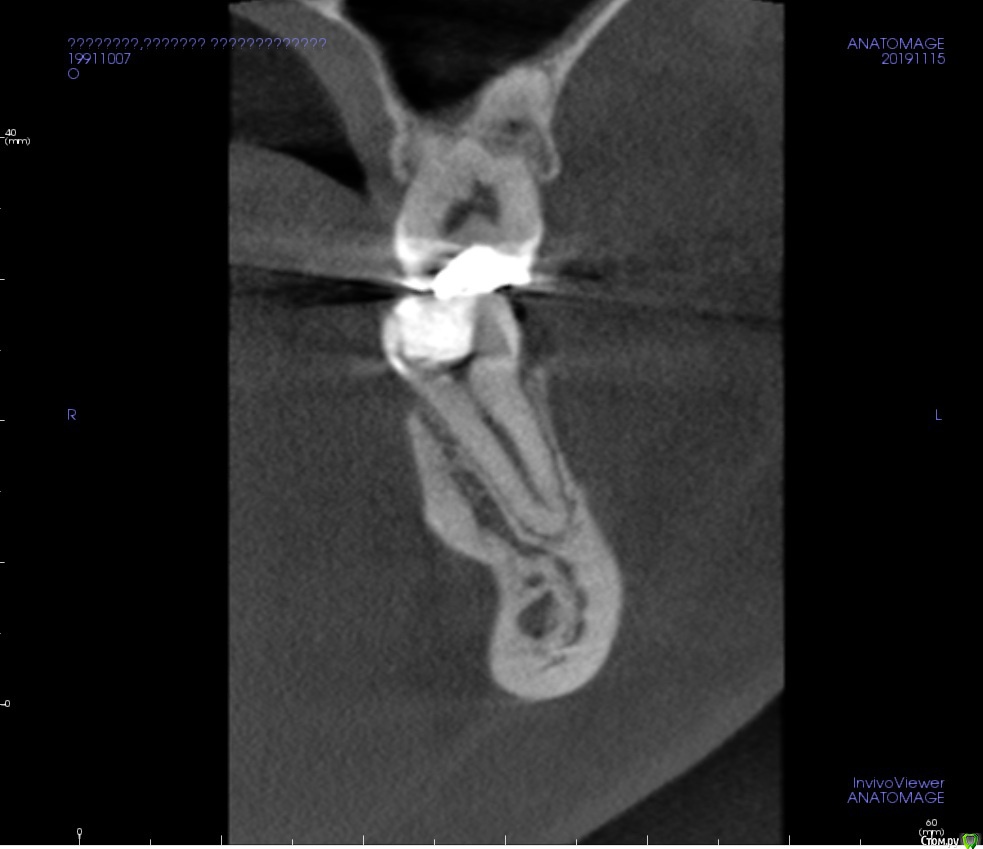

Verta Опубликовано 21 ноября, 2019 Поделиться Опубликовано 21 ноября, 2019 (изменено) Вечером разболелась половина лица, подумала на начинающийся гайморит или режущийся зуб мудрости. На 4 день боль локализовалась в нижней 6. Зуб пломбированный лет 15 назад, ранее не беспокоил, стал реагировать на холодное: рентген, пульпит. После наложения пасты реакция на холодное пропала, но при давлении на зуб сильная боль, также боль при давлении на десну под зубом только с внутренней стороны. Через 3 дня обратилась с болью- пасту переложили. После очередного приступа боли сделала КТ зуба, третий врач предположила, что это реакция на пасту. На лечении при прохождении одного канала была опять эта знакомая боль. Контрольный снимок показал правильно запломбированные каналы. И вот, спустя неделю, зуб сильно болит при накусывании, никаких изменений на дёснах нет, четыре врача не видят причины. Что делать? Снимки сделаны до лечения, ещё заложена паста Изменено 21 ноября, 2019 пользователем Verta Ссылка на комментарий

Verta Опубликовано 22 ноября, 2019 Автор Поделиться Опубликовано 22 ноября, 2019 Снимок Ссылка на комментарий